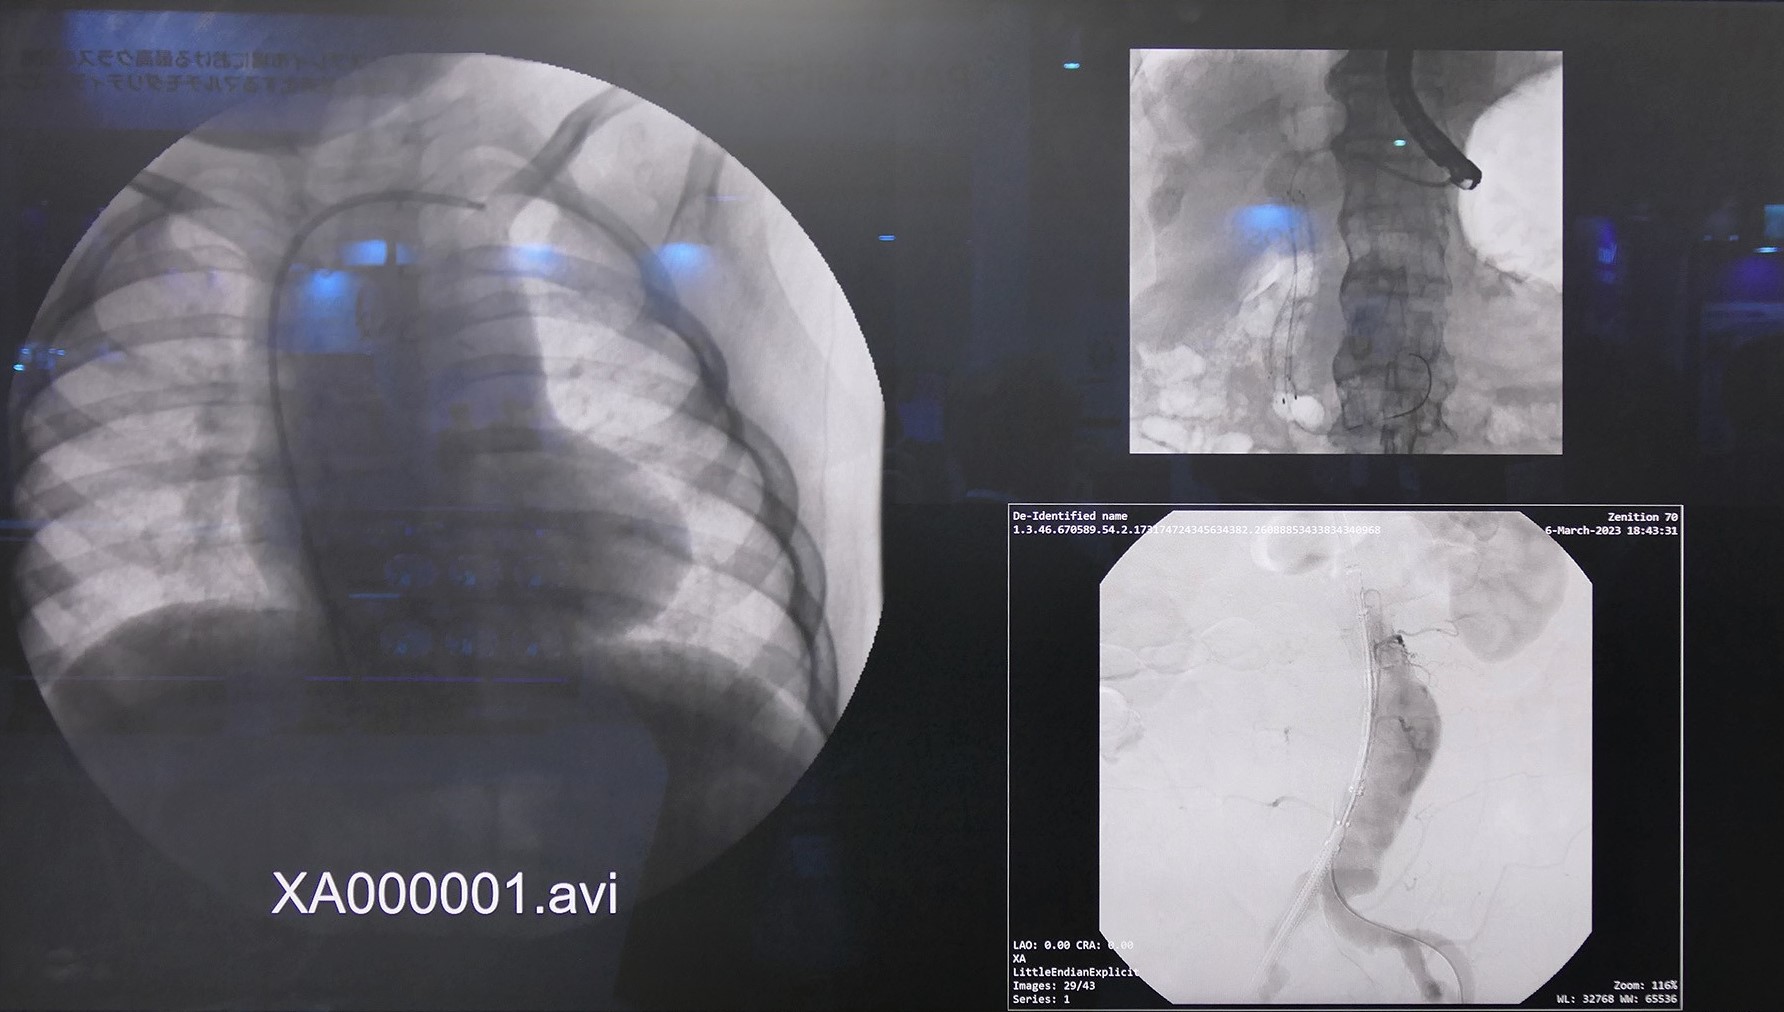

『MDAC-8355』は画像合成機能を搭載した4K 55インチ医療用液晶ディスプレイ。4つのソースを同時に入力でき、画面を合成して表示できるのが特徴。フルハイビジョン相当の画面を4つまで表示でき、4K画像の1画面表示も可能。4つの画像に対して個別にγ値や色温度を設定できる。

レイアウトを事前に設定しておけば、手元のリモコンで4分割、3分割など、使用したい環境に応じて画像を設定できる。モニター自体に合成機能があるので、付加装置は不要。